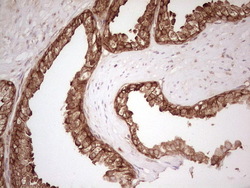

- Main image

- Experimental details

- Immunohistochemical staining of paraffin-embedded Human prostate tissue within the normal limits using anti-WIBG mouse monoclonal antibody. (Heat-induced epitope retrieval by 1 mM EDTA in 10mM Tris, pH8.5, 120C for 3min, TA806496)

- Validation comment

- IHC